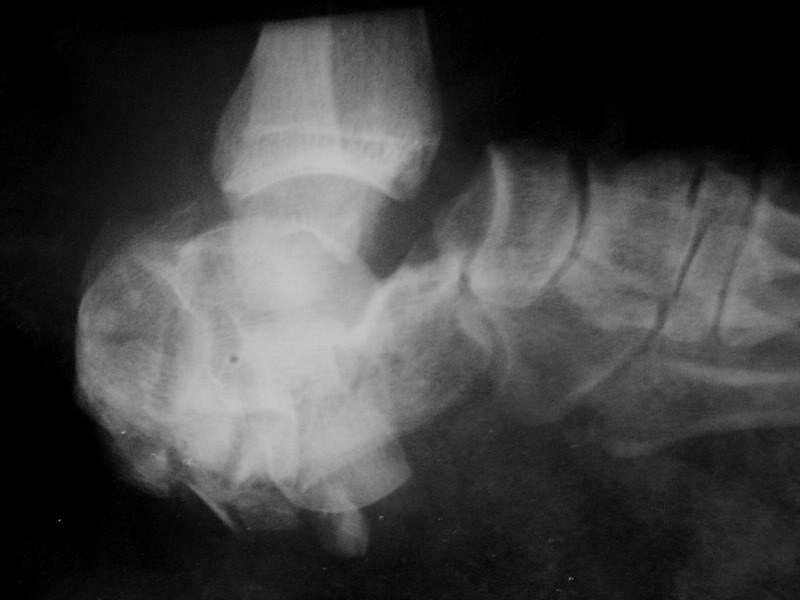

Рентгенограмма в боковой проекции приведена. В прямой проекции снимок малоинформативна (см. ниже).

Кроме того , как Вы оцениваете жизнеспособность тарана ? Представленные снимки свежие или это на момент травмы ? Как обстоит дело с нейроваскулярным статусом стопы на сегодняшний день ? Имеются ли контрольные снимки на этапах лечения (за что тянули ? на снимке вроде бы отверстие в таране) ?

Предыдущих снимков нет. Тянули, видимо, за мягкие ткани, отломки пяточной кости. Действительно, похоже на отверстие в отломках, соответствует локализации свища.